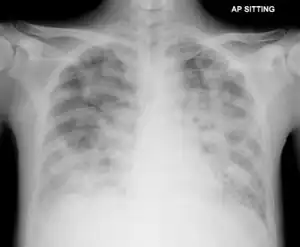

| Pneumocystosis on chest X-ray | |

Diagnosis of Pneumocystis pneumonia is by identifying the organism from a sample of sputum, fluid from affected lungs or a biopsy.[4][3] A chest X-ray of affected lungs show widespread shadowing in both lungs, with a "bat-wing" pattern and ground glass appearance.[2][7] Giemsa or silver stains can be used to identify the organism, as well as direct immunofluorescence of infected cells.[3]